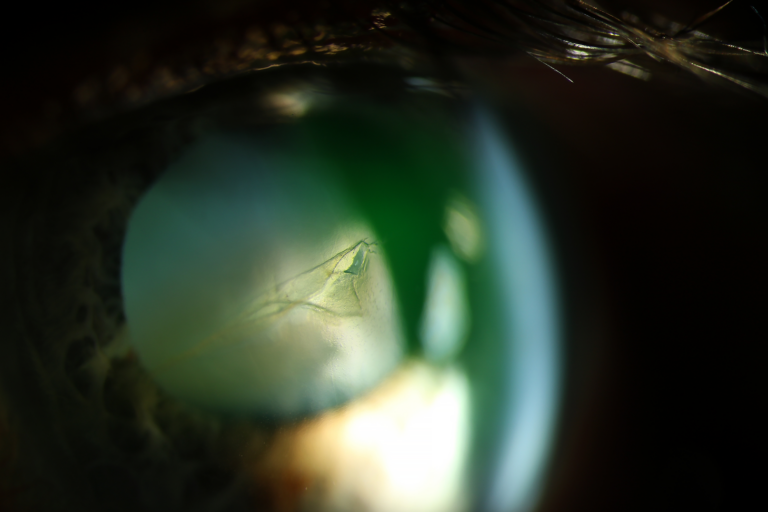

First place - Abigail James, Senior Ophthalmic Photographer, Ophthalmology, Royal Gwent Hospital, Wales

After much deliberation, winner Abigail James, a Senior Ophthalmic Photographer at Royal Gwent Hospital, reclaimed the top spot for a second year running. Not only did she win £300 in vouchers, but she secured the front cover of September’s 2025 Eye News Imaging Supplement!

Her fascinating image of a spontaneous hyphema was captured using a medium slit beam positioned to bounce light off the iris and transilluminate / highlight the hyphema’s shape and structure. Experimenting with the axis of her camera, she took the shot at 200 ISO and 1/30 shutter speed, positioning her subject oblique to emphasise the pathology’s location.